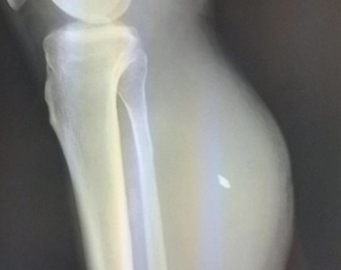

Во время обследования в правой голени мужчины обнаружили пятимиллиметровый осколок, которым была повреждена малая берцовая артерия. Также у пациента образовалась посттравматическая ложная аневризма объемом 500 миллилитров.

Разрыв ложной аневризмы может стать причиной массивного кровотечения и летального исхода. Военнослужащего экстренно госпитализирован в Ульяновскую областную клиническую больницу и успешно прооперировали.

- Наши специалисты провели резекцию аневризмы, удалили сгустки крови, выявили источник кровотечения, выполнили лигирование артерии. Оперативное вмешательство длилось более 3 часов, прошло успешно. Пациент уже самостоятельно ходит и готовится к выписке, – сообщил исполняющий обязанности заведующего торакальным сосудистым отделением Ульяновской областной клинической больницы Сергей Мустафин.

Фото - УОКБ